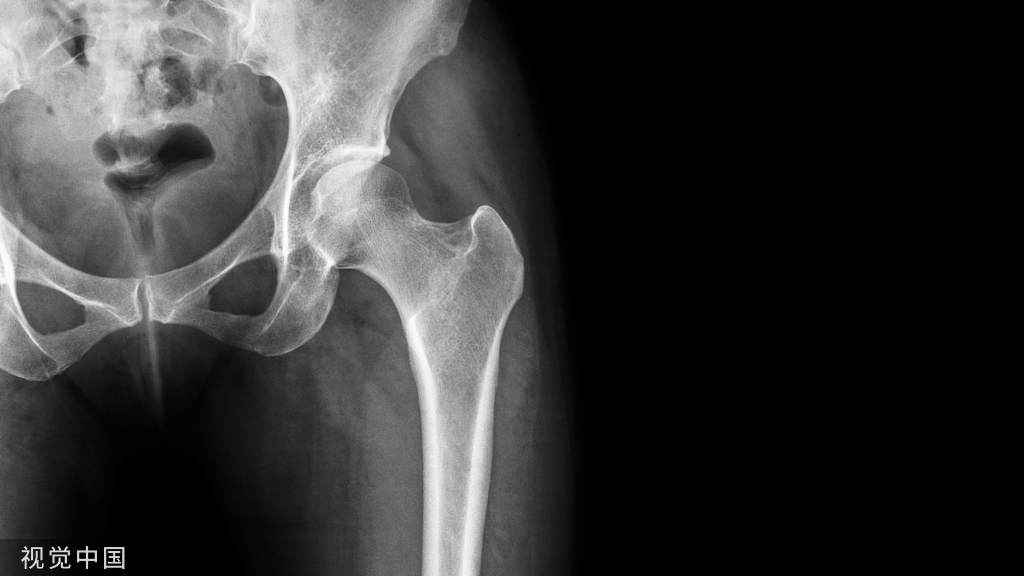

水平撕裂:它们是最常见的半月板撕裂,倾向于发生在内侧半月板的体部或后角。在40岁以上的人群中,无相关膝部损伤的退行性基础上更为常见。

图 5: 一名43岁男性,有急性膝痛病史。右膝3T MRI:(A)冠状位T2加权脂肪抑制序列和(B)及(C)矢状位PD脂肪抑制序列显示内侧半月板体部和后角高T2信号,与水平撕裂相符(箭头所示)。半月板体部向内侧副韧带位移(半月板挤压)。股骨内侧髁可见骨髓水肿(星号)。